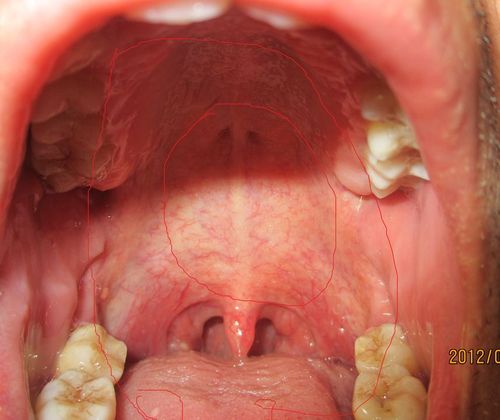

白喉口腔图片 咽喉

白喉口腔图片 咽喉,白喉口腔图片 判断

白喉口腔图片 判断

白喉口腔图片 症状

白喉口腔图片 扁桃体

白喉口腔图片

白喉病咽部图片